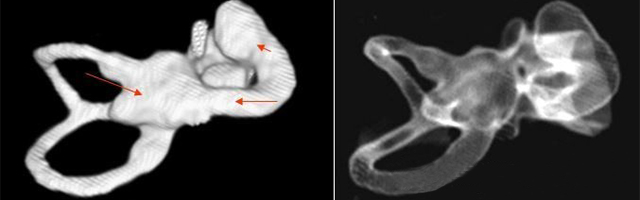

1、診斷

主要依靠顳骨高分辨CT和內(nèi)耳MRI。

雙側(cè)內(nèi)耳畸形:左側(cè)無內(nèi)耳迷路及內(nèi)耳道機(jī)構(gòu),為米歇爾畸形;右側(cè)空耳蝸及前庭擴(kuò)大,為先天性耳蝸畸形